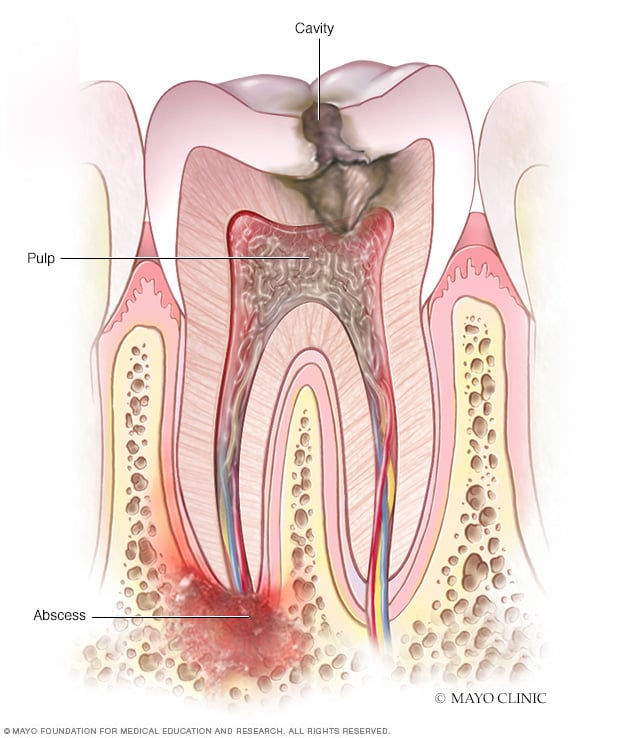

Treatment of a dental abscess | Ralev Dental Clinic

Dental abscess: What Are The Possible Treatments? – Emergency Dentist

Absceso dental – Síntomas y causas – Mayo Clinic

What is Tooth Abscess and Its Reasons? | Abscess tooth, Teeth, Nursing …

Dental Abscess or Infection | Dentist West Haven, Milford, CT

Tooth abscess symptoms: What is a dental abscess, how do you fix it …

How You Can Treat The Periodontal Abscess? – Emergency Dentist

Periodontal Abscess | Supernumerary Teeth – Hyperdontia

How to differentiate between Acute Alveolar Abscess and Periodontal Abscess

Tooth Abscess – What to do? Signs, Symptoms & Treatment – Malvern …